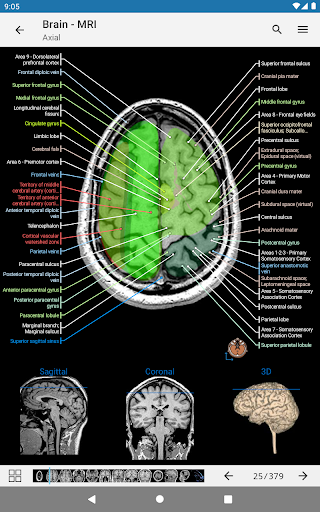

e-Anatomy memiliki lebih dari 26.000 gambar yang berisi serangkaian gambar dalam tampilan aksial, koronal, dan sagital serta radiografi, angiografi, gambar diseksi, bagan anatomi, dan ilustrasi. Semua gambar medis diberi label dengan cermat, lebih dari 967.000 label tersedia dalam 12 bahasa termasuk Terminologia Anatomica Latin.

- Gulir set gambar dengan menyeret jari Anda

- Perbesar dan perkecil

- Ketuk label untuk menampilkan struktur anatomi

- Pilih label anatomi berdasarkan kategori